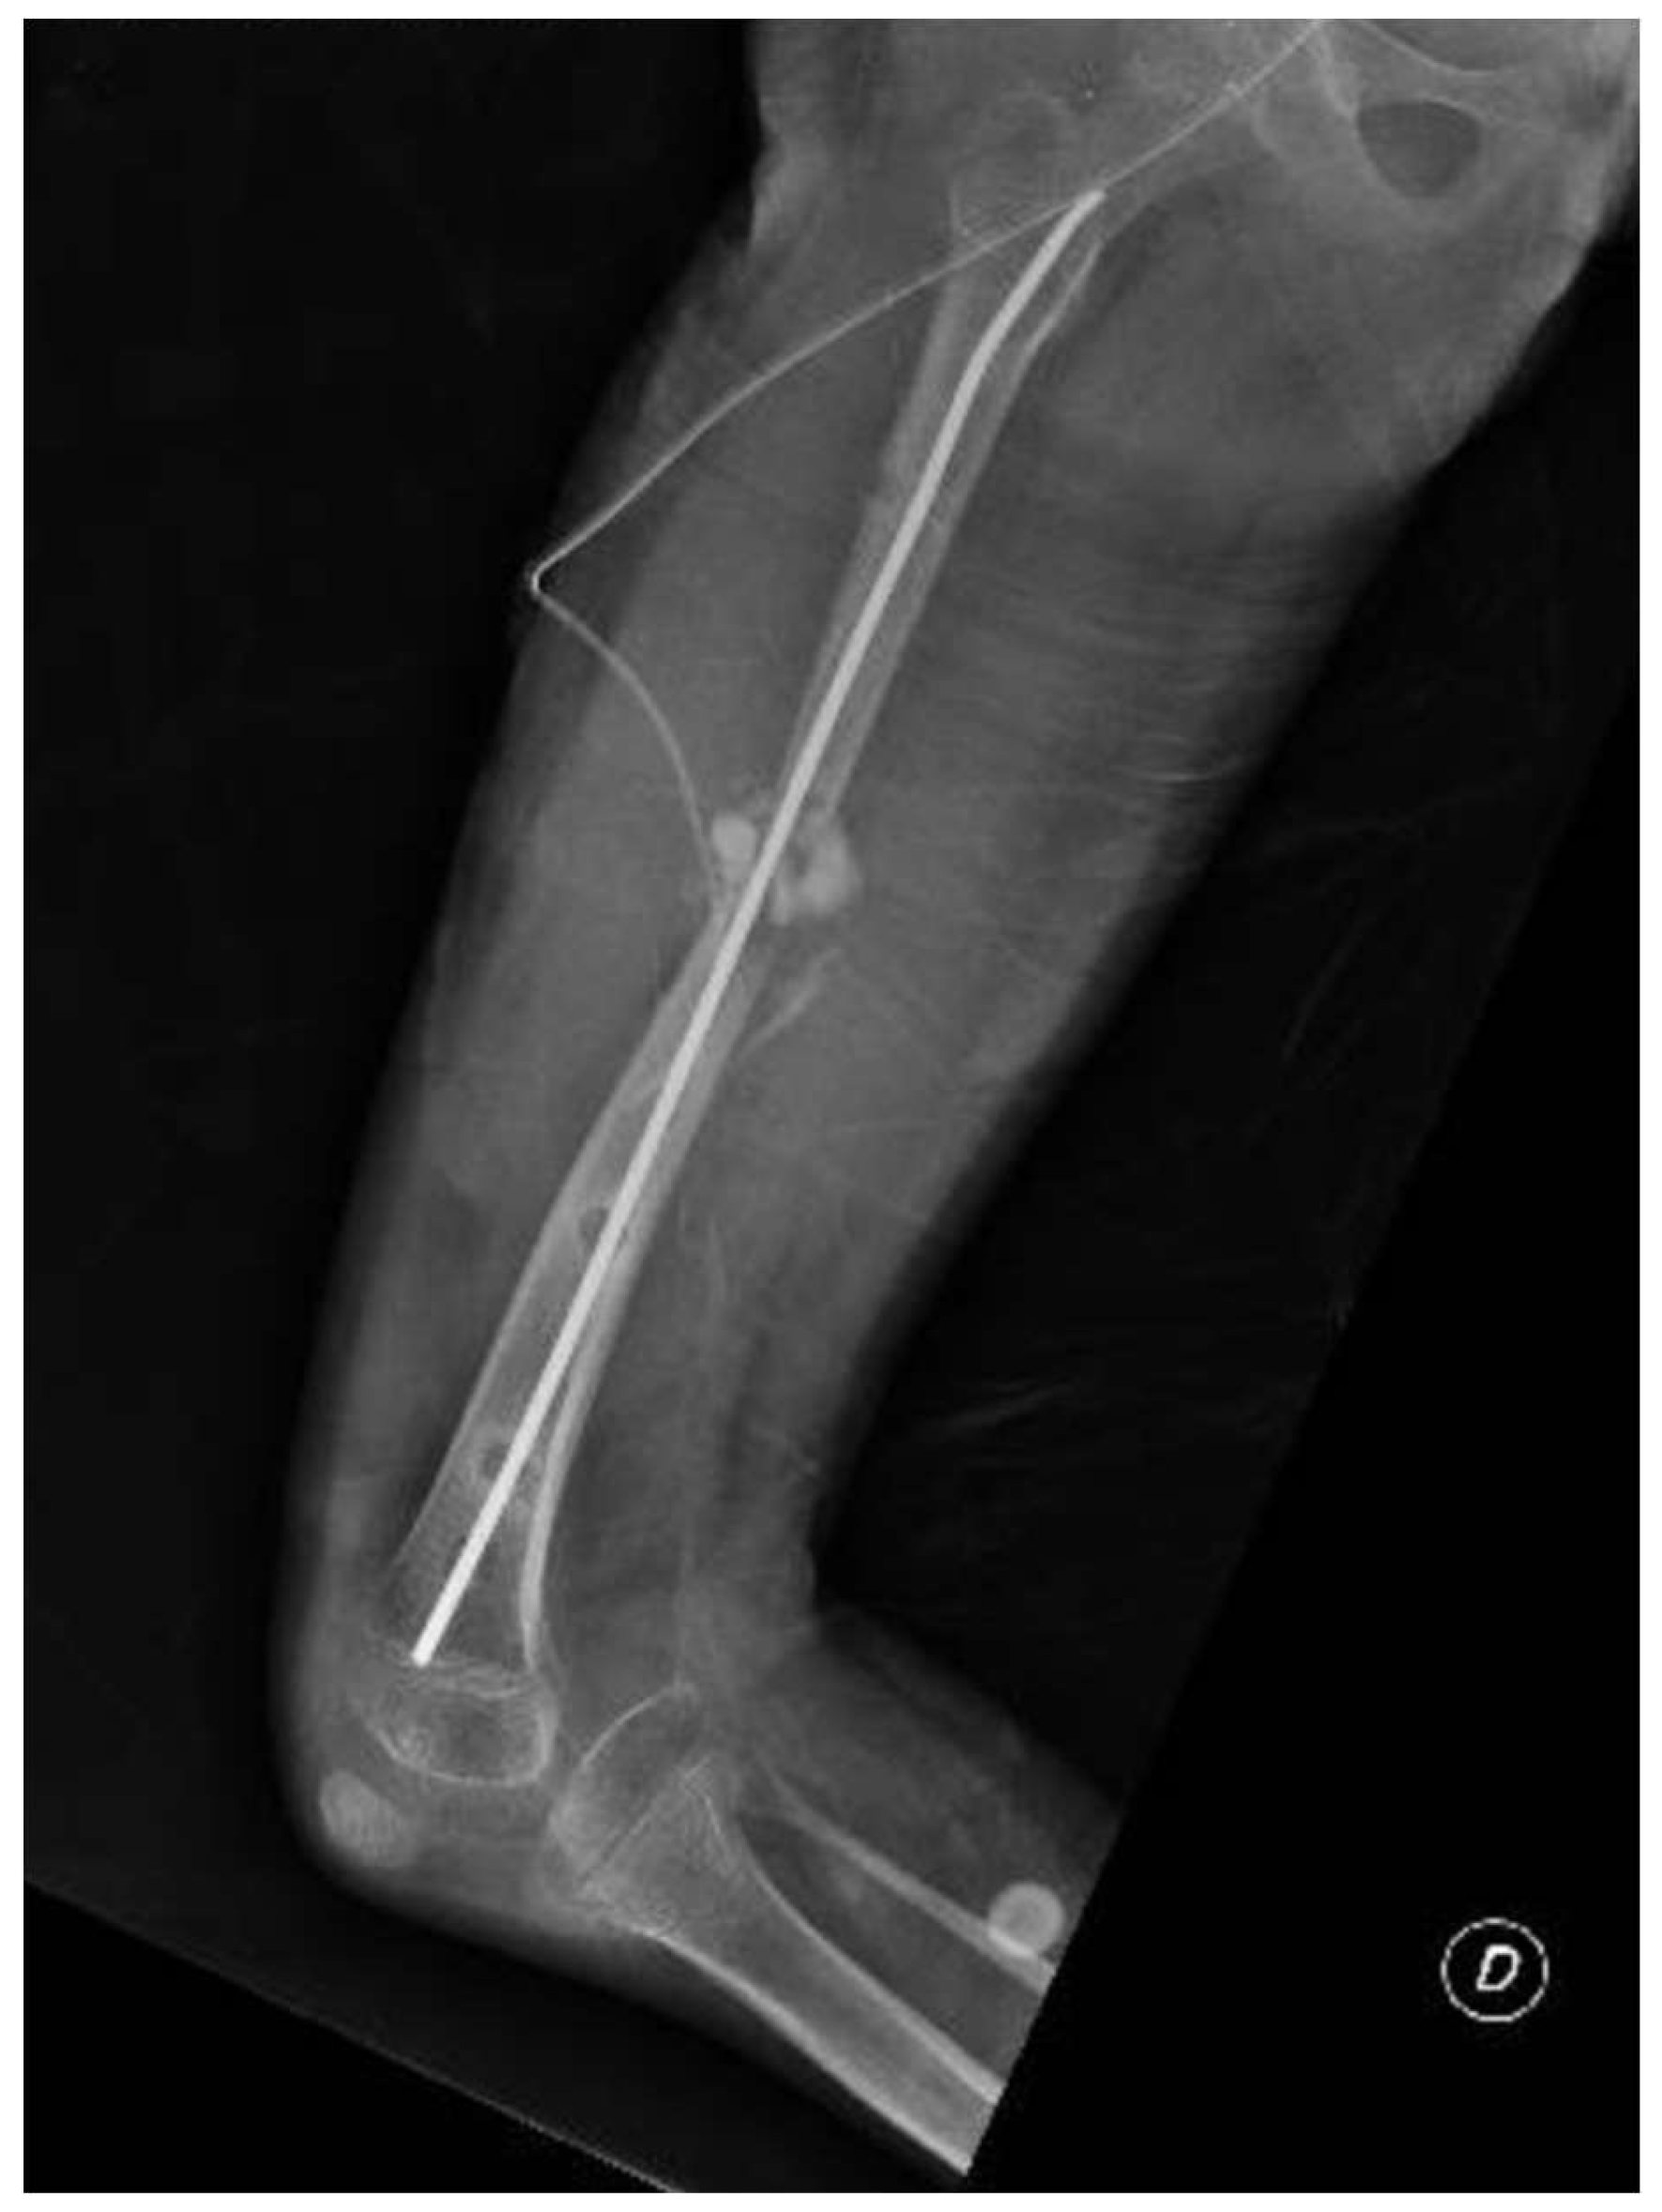

The patient presented to our attention at about 6 months post-surgery complaining of acute pain and deformity at the middle third of the thigh. Radiographs showed fracture of the femoral regenerate (Figure 4). The patient underwent immediate external fixator removal, reduction of the knee dislocation and finally Elastic Stable Intramedullary Nailing (ESIN) of the femoral fracture prior attempt to ream the femoral canal losing 20 of the 60 mm lengthened (Figure 5). Ten months after the procedure, the patient underwent nail removal for complete fracture consolidation.

Figure 5. caption.

Preprints 139634 g005